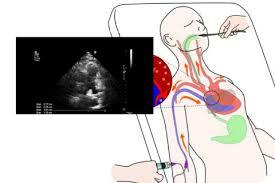

Ecocardiografía Doppler

Proporciona amplia información morfológica y funcional, pudiendo objetivar alteraciones anatómicas a nivel cardíaco, dilatación de las cavidades, arritmias, derrame pericárdico, así como obtener índices de función sistólica.

• Ecocardiografía pulmonar

Ecocardiografía pulmonar

La evaluación de la patología pulmonar en tiempo

real. Recientemente, se ha incrementado su uso en niños para

el estudio de patologías del pulmón, pleura y diafragma. La

ventaja en este grupo de pacientes se origina en la falta de

osificación.